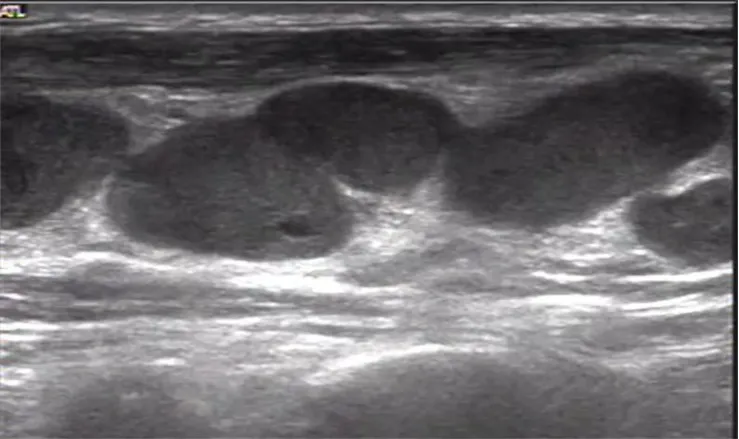

淋巴结结核

● 淋巴结不同程度肿大,多呈椭圆形,近圆形,纵横比>2。

● 被膜完整或不完整,淋巴结之间可融合成串珠样。

● 内部回声不均匀,以低回声为主,可见斑片状强回声,髓质偏心或显示不清。

● 淋巴结内血流信号增多、杂乱,干酪样坏死、脓肿区则无血流信号,可显示边缘少量血流信号。

● 脓肿形成时可见含细点状或絮状回声不规则液性暗区,加压可见流动,脓肿可突破包膜。

左腋下淋巴结结核样肉芽肿性炎并坏死及钙化。

病例:1岁男孩,发现腋窝包块2个月,质地较硬,患儿无明显发热。

超声描述:左侧腋窝可见两个混合回声团,边界清楚,内部回声不均匀,可见多个强回声点,未见明显淋巴结结构。内部见杂乱血流信号。